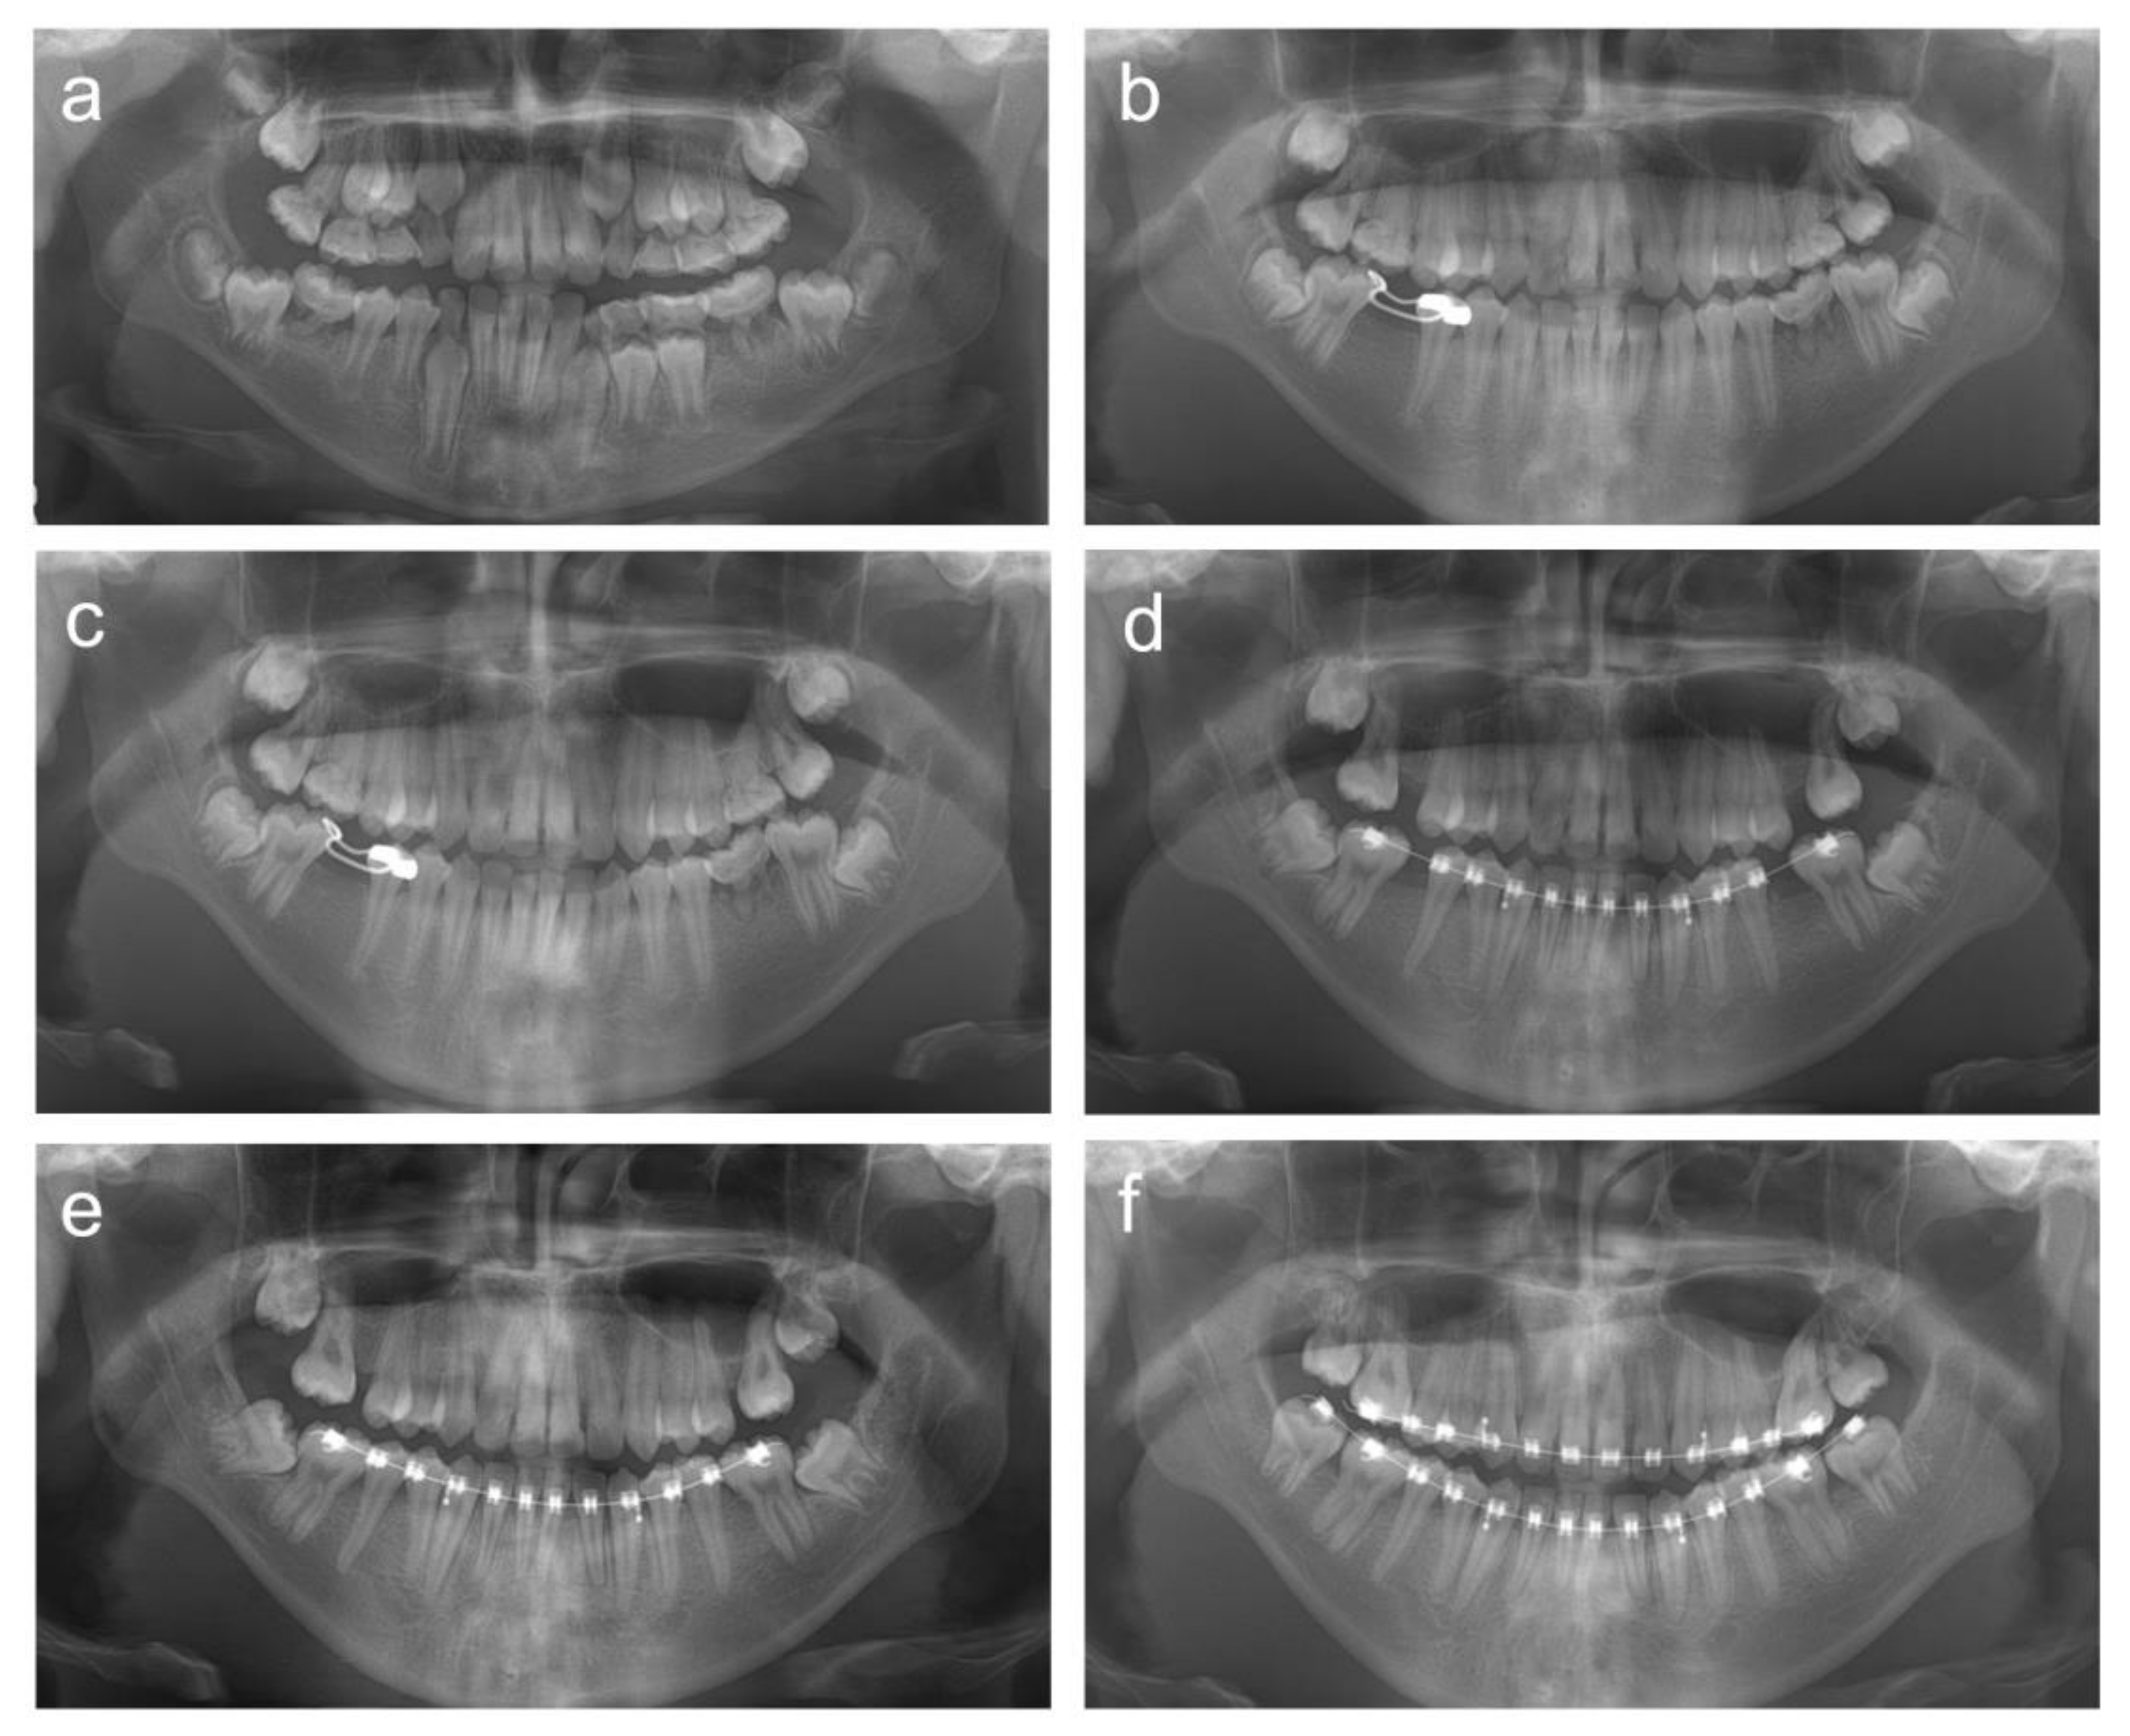

2. Cases

2.1. Case 1

2.2. Case 2

2.3. Case 3

2.4. Case 4

2.5. Case 5